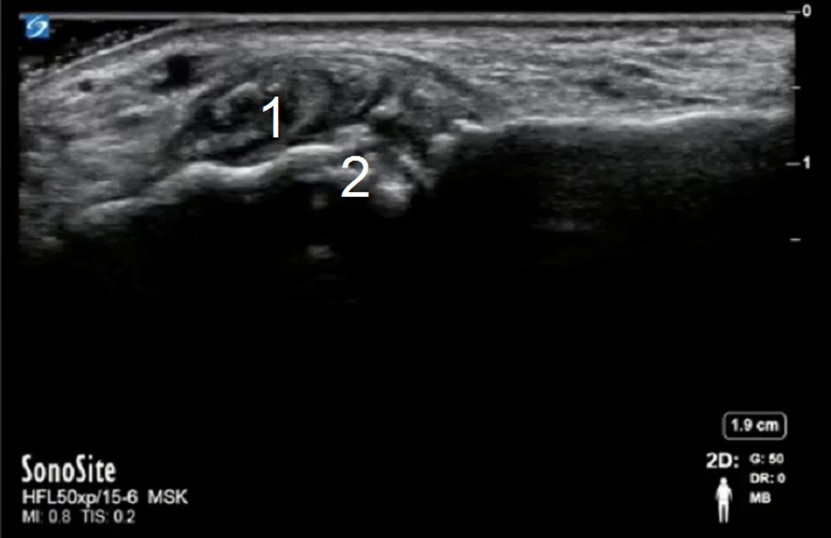

Foot & Ankle Tophus and Erosion Image

Tophus

Bone Erosion